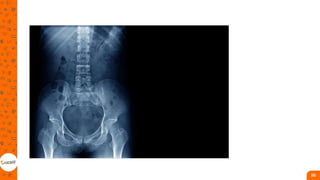

Estudo de imagem na prática da fisioterapia

RADIOGRAFIA

• a imagem desse tipo exame é

formada por feixes de raios X

que são absorvidos ou não de

acordo com a estrutura do

corpo. Tais raios interagem com

a matéria por meio de seu

campo elétrico oscilante com os

elétrons atômicos no material

• As radiografias simples são

geradas quando um filme de raio

X é exposto à radiação ionizante

e desenvolvido por processo

fotoquímico;

• A principal vantagem das

radiografias é que são

produções relativamente baratas

e ainda são os estudos de

imagem mais amplamente

utilizados.